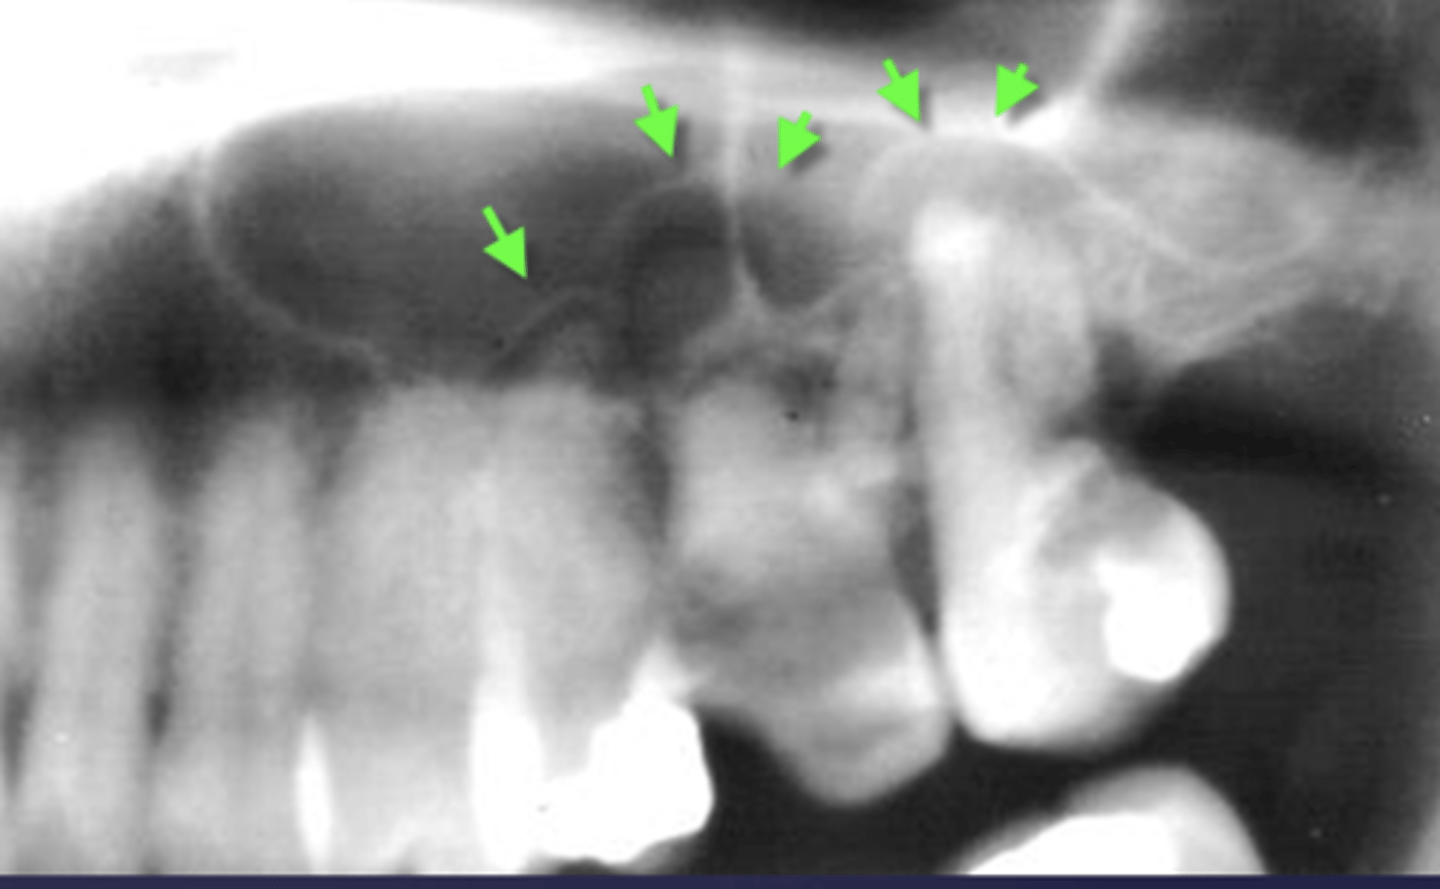

What are two defects that the arrows are pointing to?

- Widened PDL

- Sclerosis

What are the arrows pointing to?

halo sign